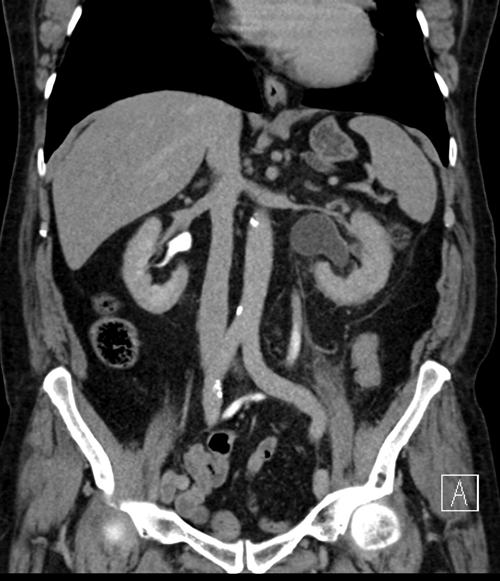

Case 9

- There is right hydronephrosis and perinephric fat stranding adjacent to the right kidney. Air is seen in the collecting system and there are multiple calculi in the right kidney.

- The appearance has a description of a ‘bear’s paw’.

- The diagnosis is xanthogranulomatous pyelonephritis. This is seen in a chronically infected, obstructed kidney, and 80% of cases have renal calculi. The commonest causative organisms are Proteus and E coli. It is often associated with diabetes, or seen in immunocompromised patients. It usually affects the whole kidney, but 15% of cases can be focal.

- Antibiotics should be given, but surgical treatment with nephrectomy is usually required. The affected kidney is usually non-functioning, and patients are often systemically unwell due to the chronic nature of the condition.